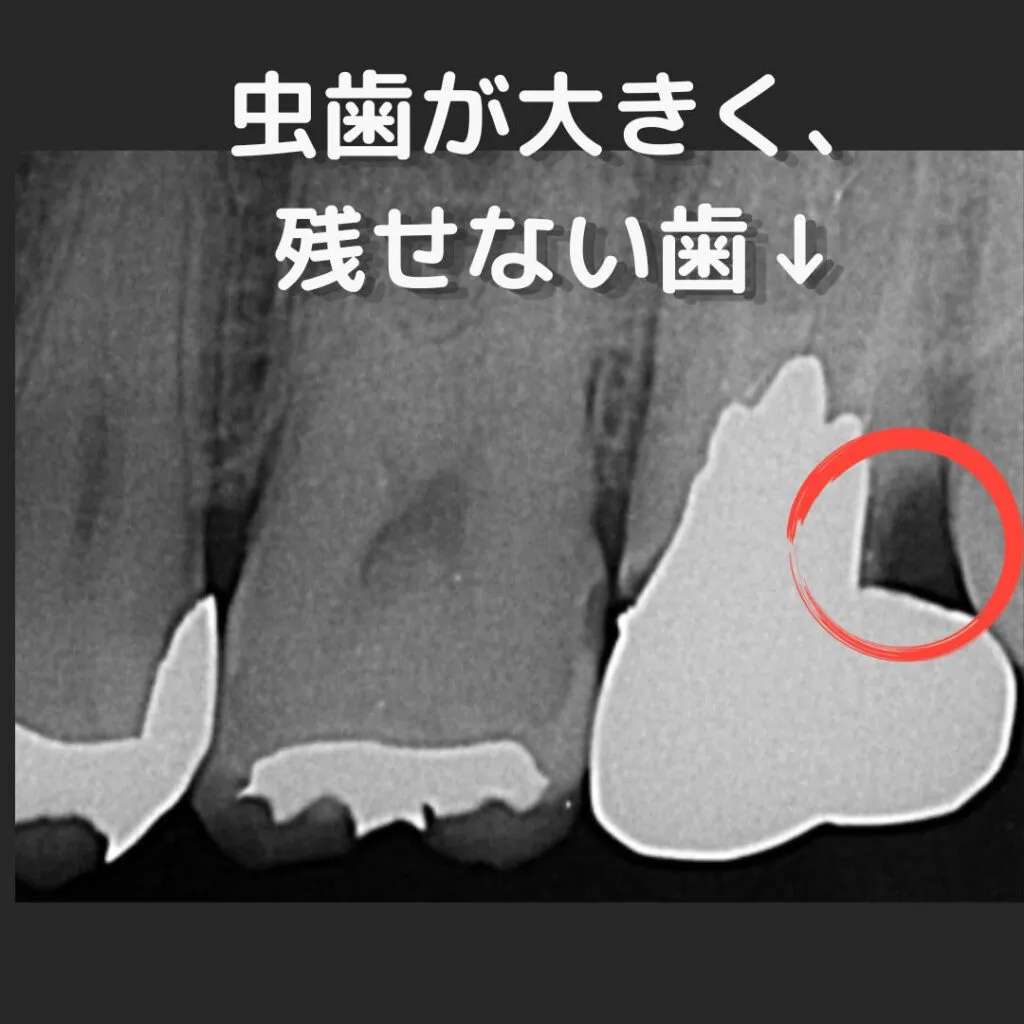

症例1(虫歯が大きく残せないため、親知らずを移植しました)

| 治療のリスクについて | タバコは傷の治りを悪くします。 出来るだけ禁煙していただくか、本数を減らしていただけるようお願いします。 静脈が多い所を切るので、内出血や腫れることがあります。 術後すぐは、歯が少し揺れます。 |

|---|---|

| 費用 | 移植手術…………………………………………………66,000円 顕微鏡を使用しての神経処置…………………………66,000円 被せ物(ジルコニア)………………………………126,500円 合計……………………………………………………258,500円 |

※すべて税込